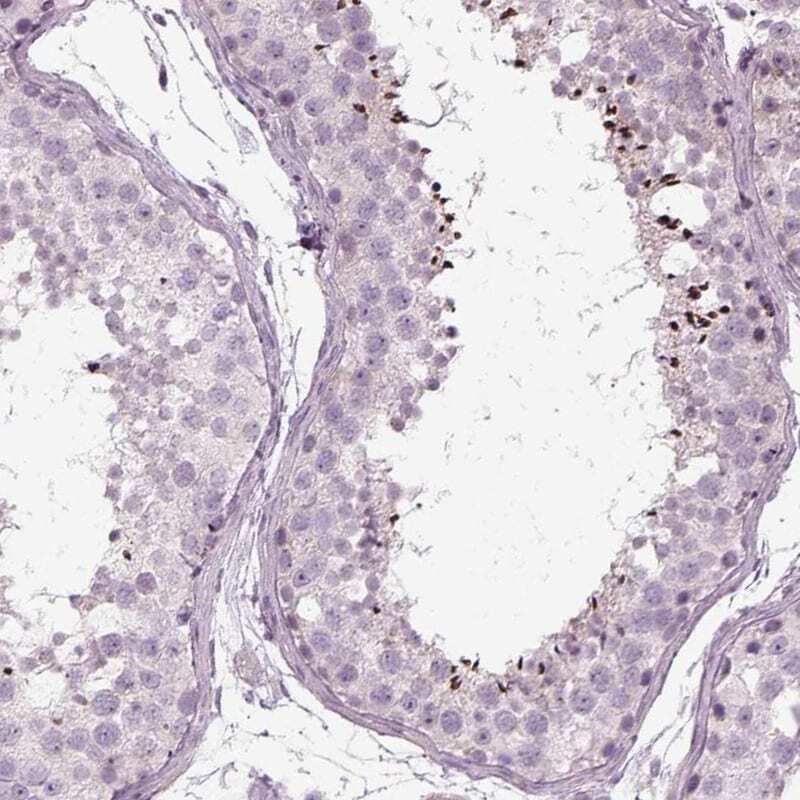

Supportive validation

- Submitted by

- Invitrogen Antibodies (provider)

- Main image

- Experimental details

- Immunohistochemical staining of LRRIQ3 in human testis using a LRRIQ3 Polyclonal Antibody (Product # PA5-56562) shows strong cytoplasmic positivity in spermatozoa.